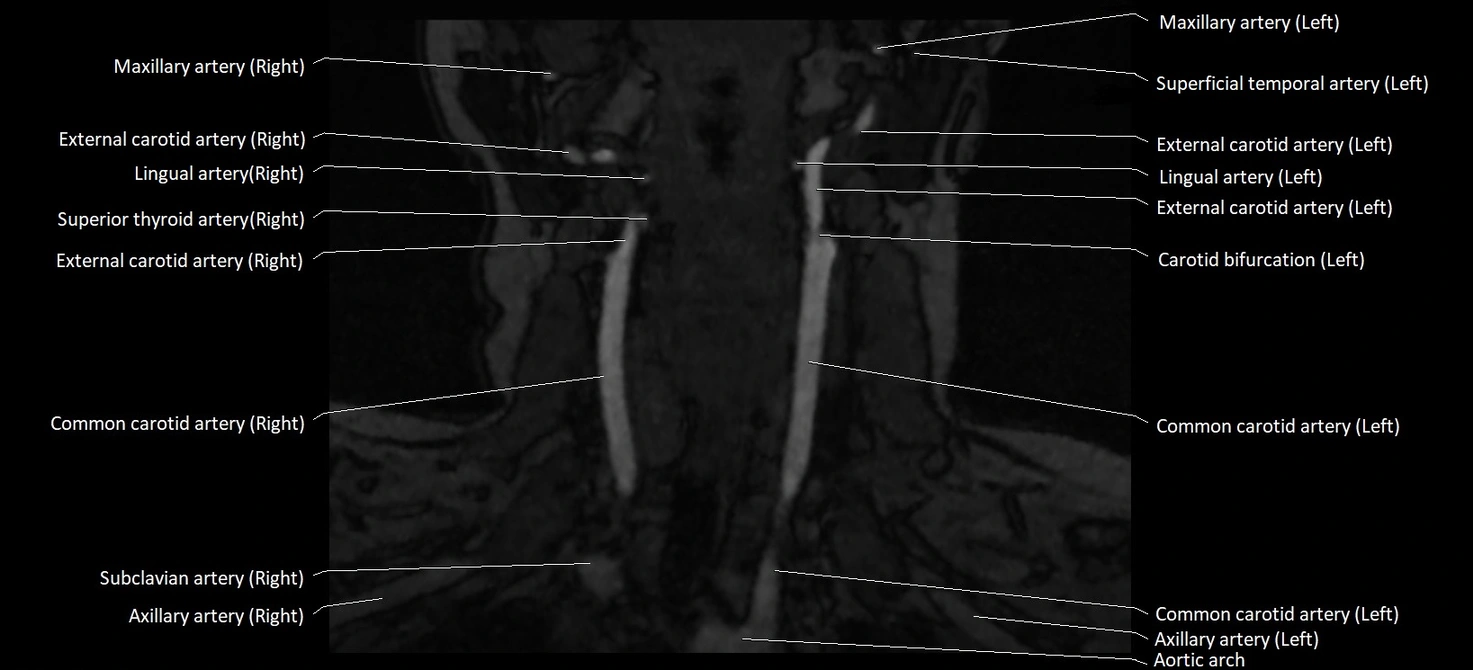

MRI images

image